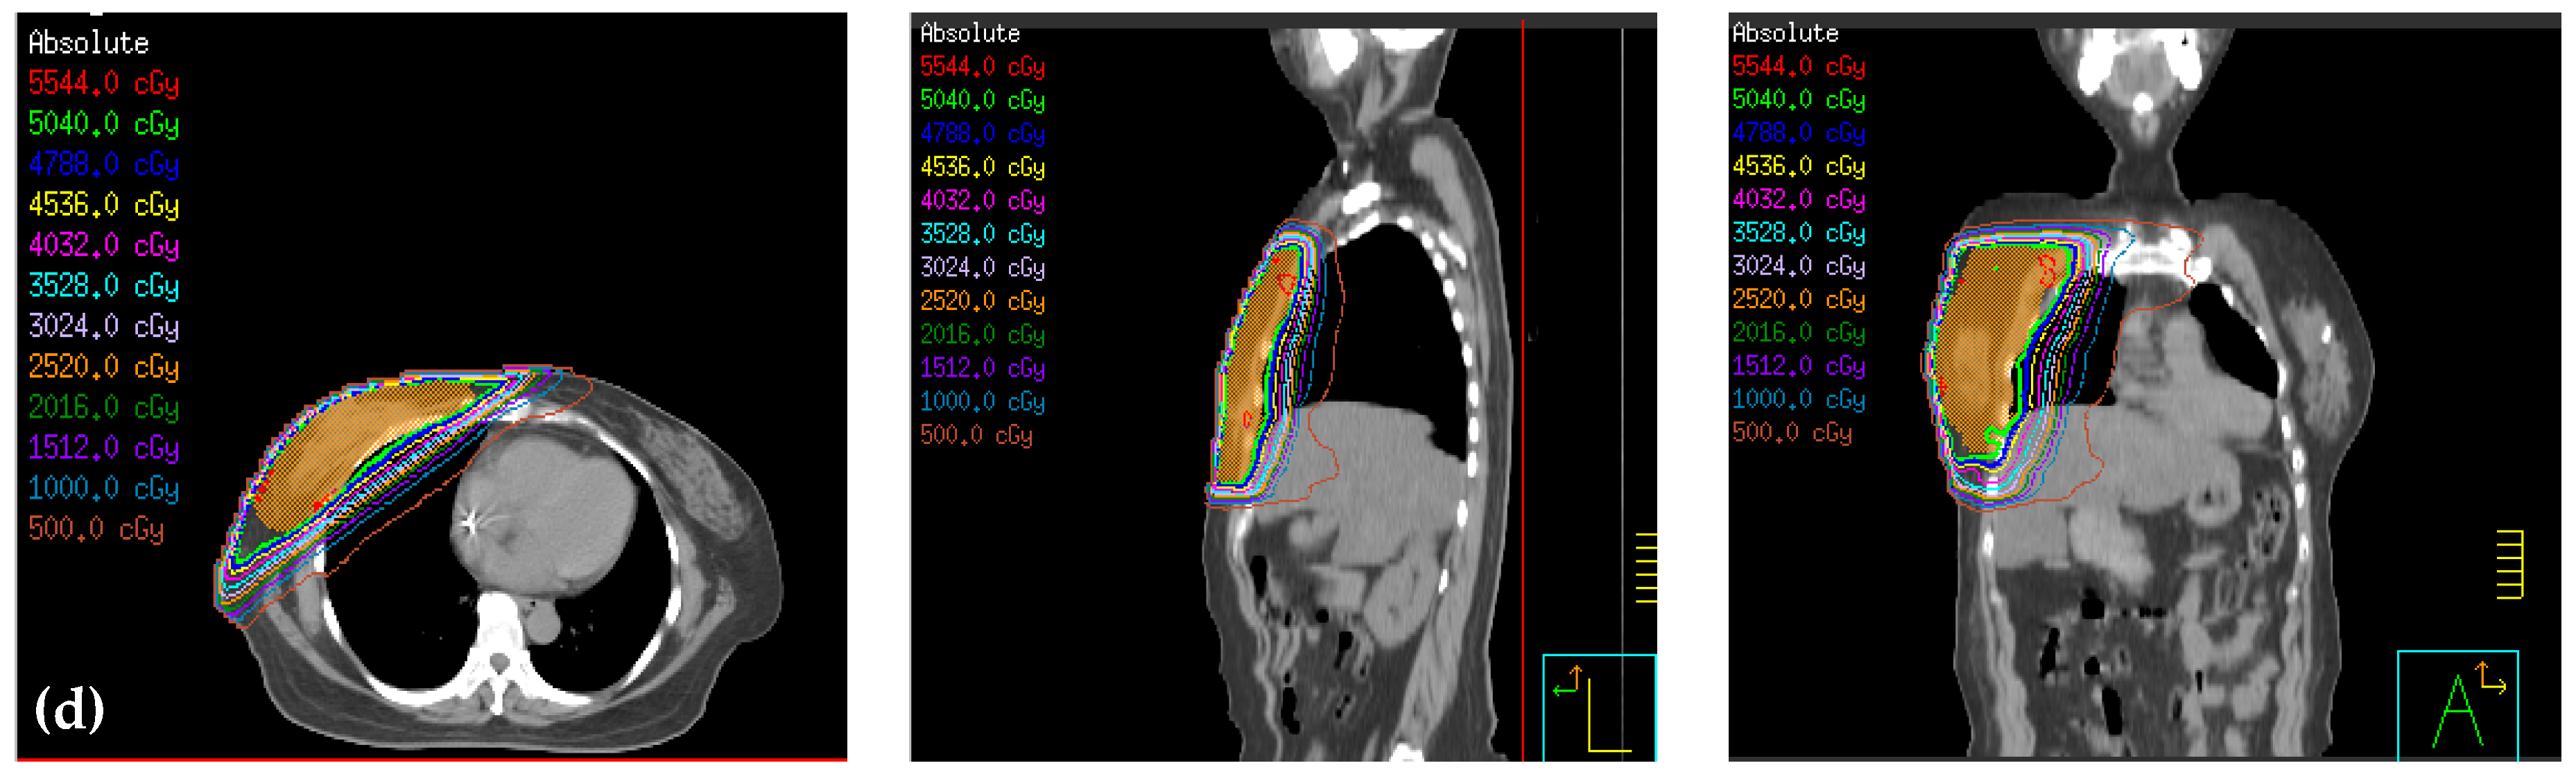

3.1. Comparison of Reduced PTV (rPTV) in Four Techniques on Dosimetry

| Structures | Continuous Partial Arc | Non-Continuous Partial Arc | Hybrid 3D-CRT/IMRT | IMRT |

|---|---|---|---|---|

| Mean dose (Gy) | 52.05 ± 0.09 | 51.61 ± 1.33 | 51.82 ± 1.52 | 51.81 ± 1.45 |

| Maximum dose (Gy) | 55.88 ± 0.16 | 55.07 ± 0.08 | 56.15 ± 0.07 | 55.52 ± 0.08 |

| minimal dose (Gy) | 25.60 ± 0.16 | 23.69 ± 1.23 | 21.67 ± 0.15 | 23.00 ± 0.04 |

| V100 (%) | 97.42 ± 0.09 | 92.39 ± 0.23 | 87.61 ± 1.23 | 89.12 ± 1.43 |

| V95 (%) | 97.42 ± 0.07 | 97.41 ± 0.9 | 95.77 ± 1.18 | 96.62 ± 2.01 |

| V105 (%) | 18.59 ± 0.14 | 18.81 ± 0.11 | 15.31 ± 1.01 | 14.39 ± 1.54 |

| V107 (%) | 2.05 ± 0.06 | 0.78 ± 0.04 | 2.44 ± 0.10 | 2.38 ± 0.07 |

| V110 (%) | 0.10 ± 0.11 | 0.00 ± 0.00 | 0.02 ± 0.01 | 0.01 ± 0.01 |

| D2 (Gy) | 53.93 ± 1.45 | 53.60 ± 2.73 | 54.25 ± 1.61 | 54.25 ± 1.48 |

| D98 (Gy) | 47.21 ± 0.98 | 47.15 ± 1.44 | 45.67 ± 1.77 | 46.4 ± 1.22 |

| CI | 0.74 ± 0.01 | 0.74 ± 0.01 | 0.68 ± 0.03 | 0.64 ± 0.05 |

| HI1 | 0.79 ± 0.02 | 0.89 ± 0.11 | 0.71 ± 0.21 | 0.78 ± 0.11 |

| HI2 | 13.33 ± 0.01 | 12.79 ± 0.03 | 17.02 ± 0.03 | 15.57 ± 0.04 |